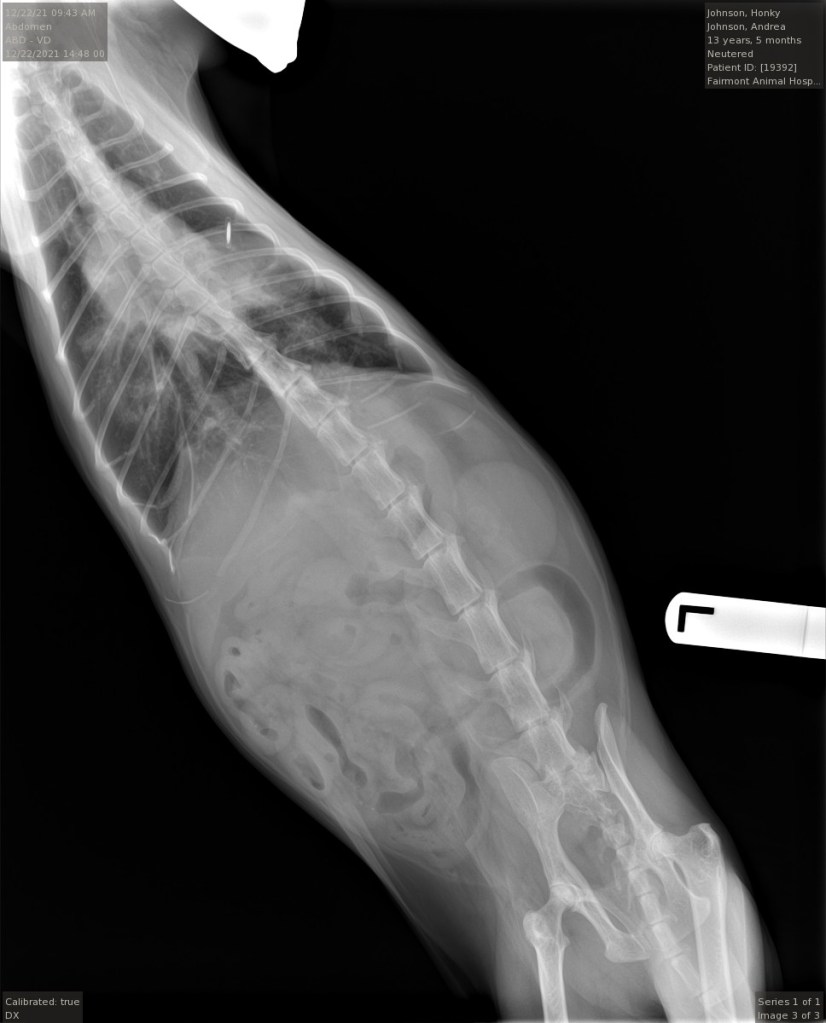

The vet, a new guy I had never dealt with before, came back into the room with a serious look on his face. He showed me the digital Xray, which showed a bigger-than-a-chicken-egg-sized mass on Honky’s right lung, right under his microchip. Cancer. There were smaller opaque areas that appeared to have infiltrated the bronchial airways. It was obvious why Honky hadn’t been feeling so great. This would be big for a mass on a human lung. It was also obvious that no surgery could treat this.

The vet came in. She has seen me through 3 out of 4 euthanasias. I asked her to have a look at the Xrays and tell me exactly what SHE saw. She came back after a couple of minutes. She said she saw the mass, and the other concerning areas, and that this was very serious. She kindly said that she thought that I was making the right choice. I thanked her and told her I really needed to know there was no hope.